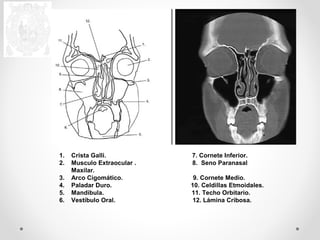

1. Crista Galli. 7. Cornete Inferior.

2. Musculo Extraocular . 8. Seno Paranasal

Maxilar.

3. Arco Cigomático. 9. Cornete Medio.

4. Paladar Duro. 10. Celdillas Etmoidales.

5. Mandíbula. 11. Techo Orbitario.

6. Vestíbulo Oral. 12. Lámina Cribosa.